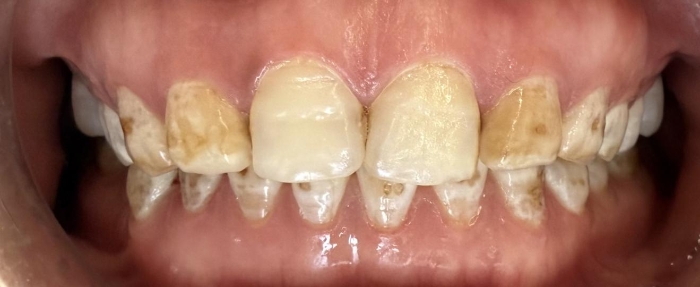

党秀医生接诊,为她进行了全面的口腔检查和美学评估。患者牙齿牙面呈深黄色斑块状,唇侧釉质多处片状缺损,边缘粗糙,部分区域浅层牙本质暴露,进冷热食物时常有不适。其余牙齿也存在不同程度的色素沉着,整体颜色晦暗。结合病史及临床检查,诊断为重度氟斑牙伴牙釉质缺损。

针对患者“既要恢复功能,又要美观自然”的诉求,党秀定制了“全口牙齿美白+美学修复”的诊疗方案。首先,对全口牙齿进行渗透树脂美白,将基础牙齿色调提亮2-3个色阶,使其他牙齿与后续贴面修复后的上前牙颜色协调;其次,开展上前牙贴面美学修复,制作超薄瓷贴面,恢复牙体外形、遮色并重建缺损的釉质层。全程治疗周期约10天,患者无明显不适。